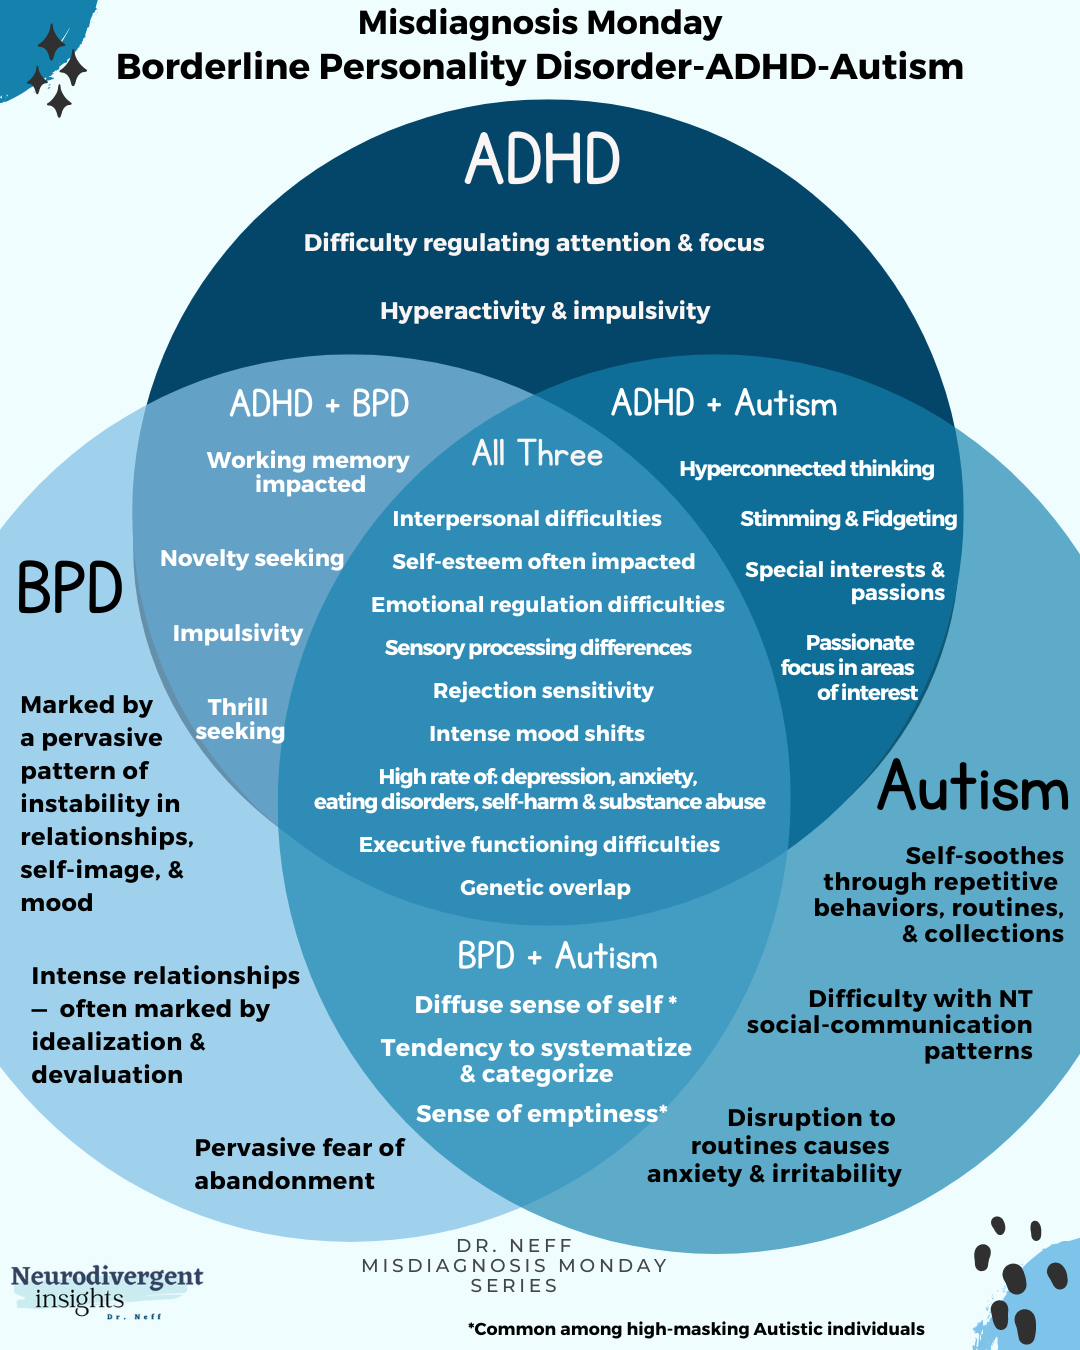

BPD, ADHD, and Autism